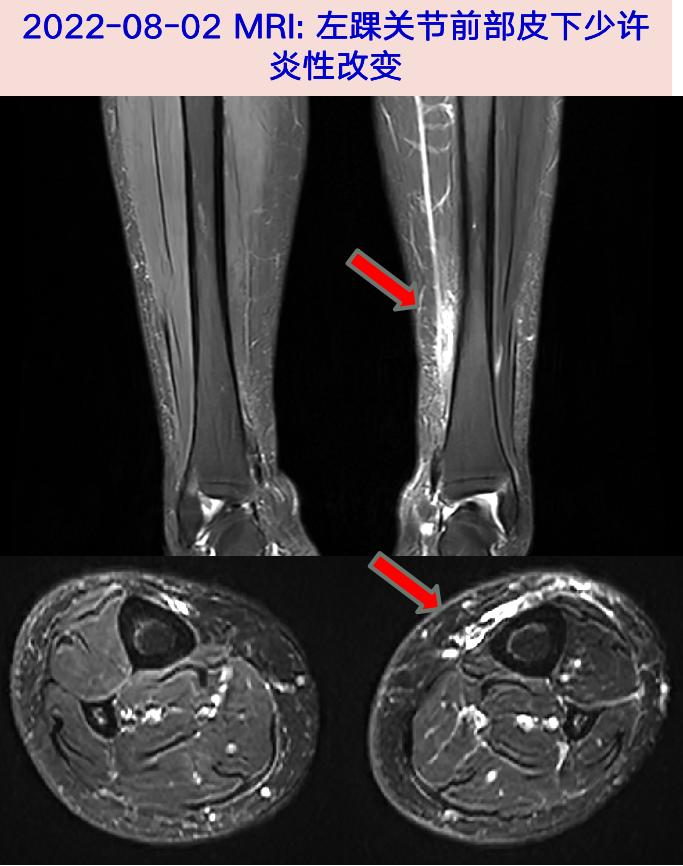

2022-08-02 伤口分泌物拭子细菌、真菌培养阴性;2022-08-02 左下肢软组织平扫+增强MRI: 左踝关节前部皮下少许炎性改变,双踝关节退变伴少量积液。

中年女性,左下肢猫咬伤后红肿热痛,伴流脓、发热,经验性抗感染伤口愈合不佳,MRI见左踝关节前部皮下少许炎性改变。伤口组织mNGS检出大量多杀巴斯德菌、混合厌氧菌,予以多西环素联合哌拉西林他唑巴坦抗感染、清创后体温转平,伤口渗出逐渐减少;出院后予左氧氟沙星+甲硝唑继续抗感染,伤口愈合,故诊断明确。